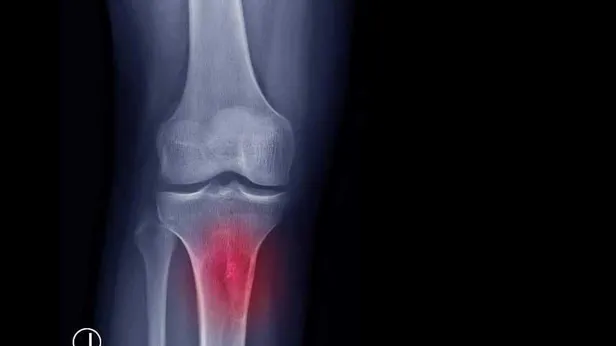

ŞİŞLİK:Hastanın özellikle diz, omuz ve kalça çevresinde düzensiz sınırlı, sert, hareketsiz ve hızlı büyüyen şişlik gelişir. Şişliğin ağrılı olması, kötü huylu olma açısından uyarıcı olmalı ve ağrı kesicilerle geçiştirilmeyip mutlaka en kısa zamanda hekime başvurulması gerekir.

KIRIK:Ağrı ve şişlik kadar sık görülmese de hem iyi hem de kötü huylu kemik tümörü kendiliğinden kemikte kırığa yol açabilir. Her ikisi de yerleştiği kemikte yıkıma neden olabilir.